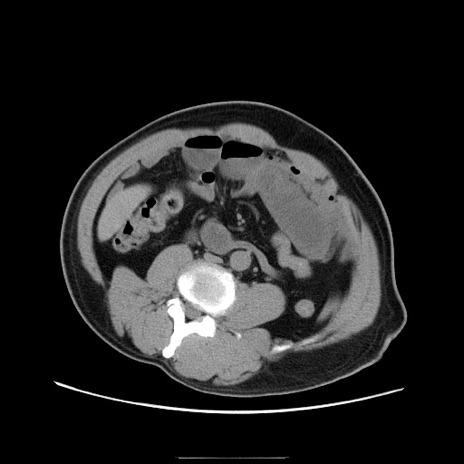

症例22(横断像)

【症例】50歳代男性

【主訴】腹痛

【現病歴】AVMからの被殻出血のため回復期リハ病棟入院中。 本日午後3時頃急に下腹部痛が出現した。

【既往歴】AVM、被殻出血、虫垂炎、高血圧

【身体所見】意識晴明、左半身不全麻痺、会話の理解は良好、36.5°C、腹部:膨隆、全体に板状硬、下腹部正中に圧痛点あり、反跳痛-、筋性防御不明、右下腹部にope scar

【データ】WBC 9400、CRP 0.06